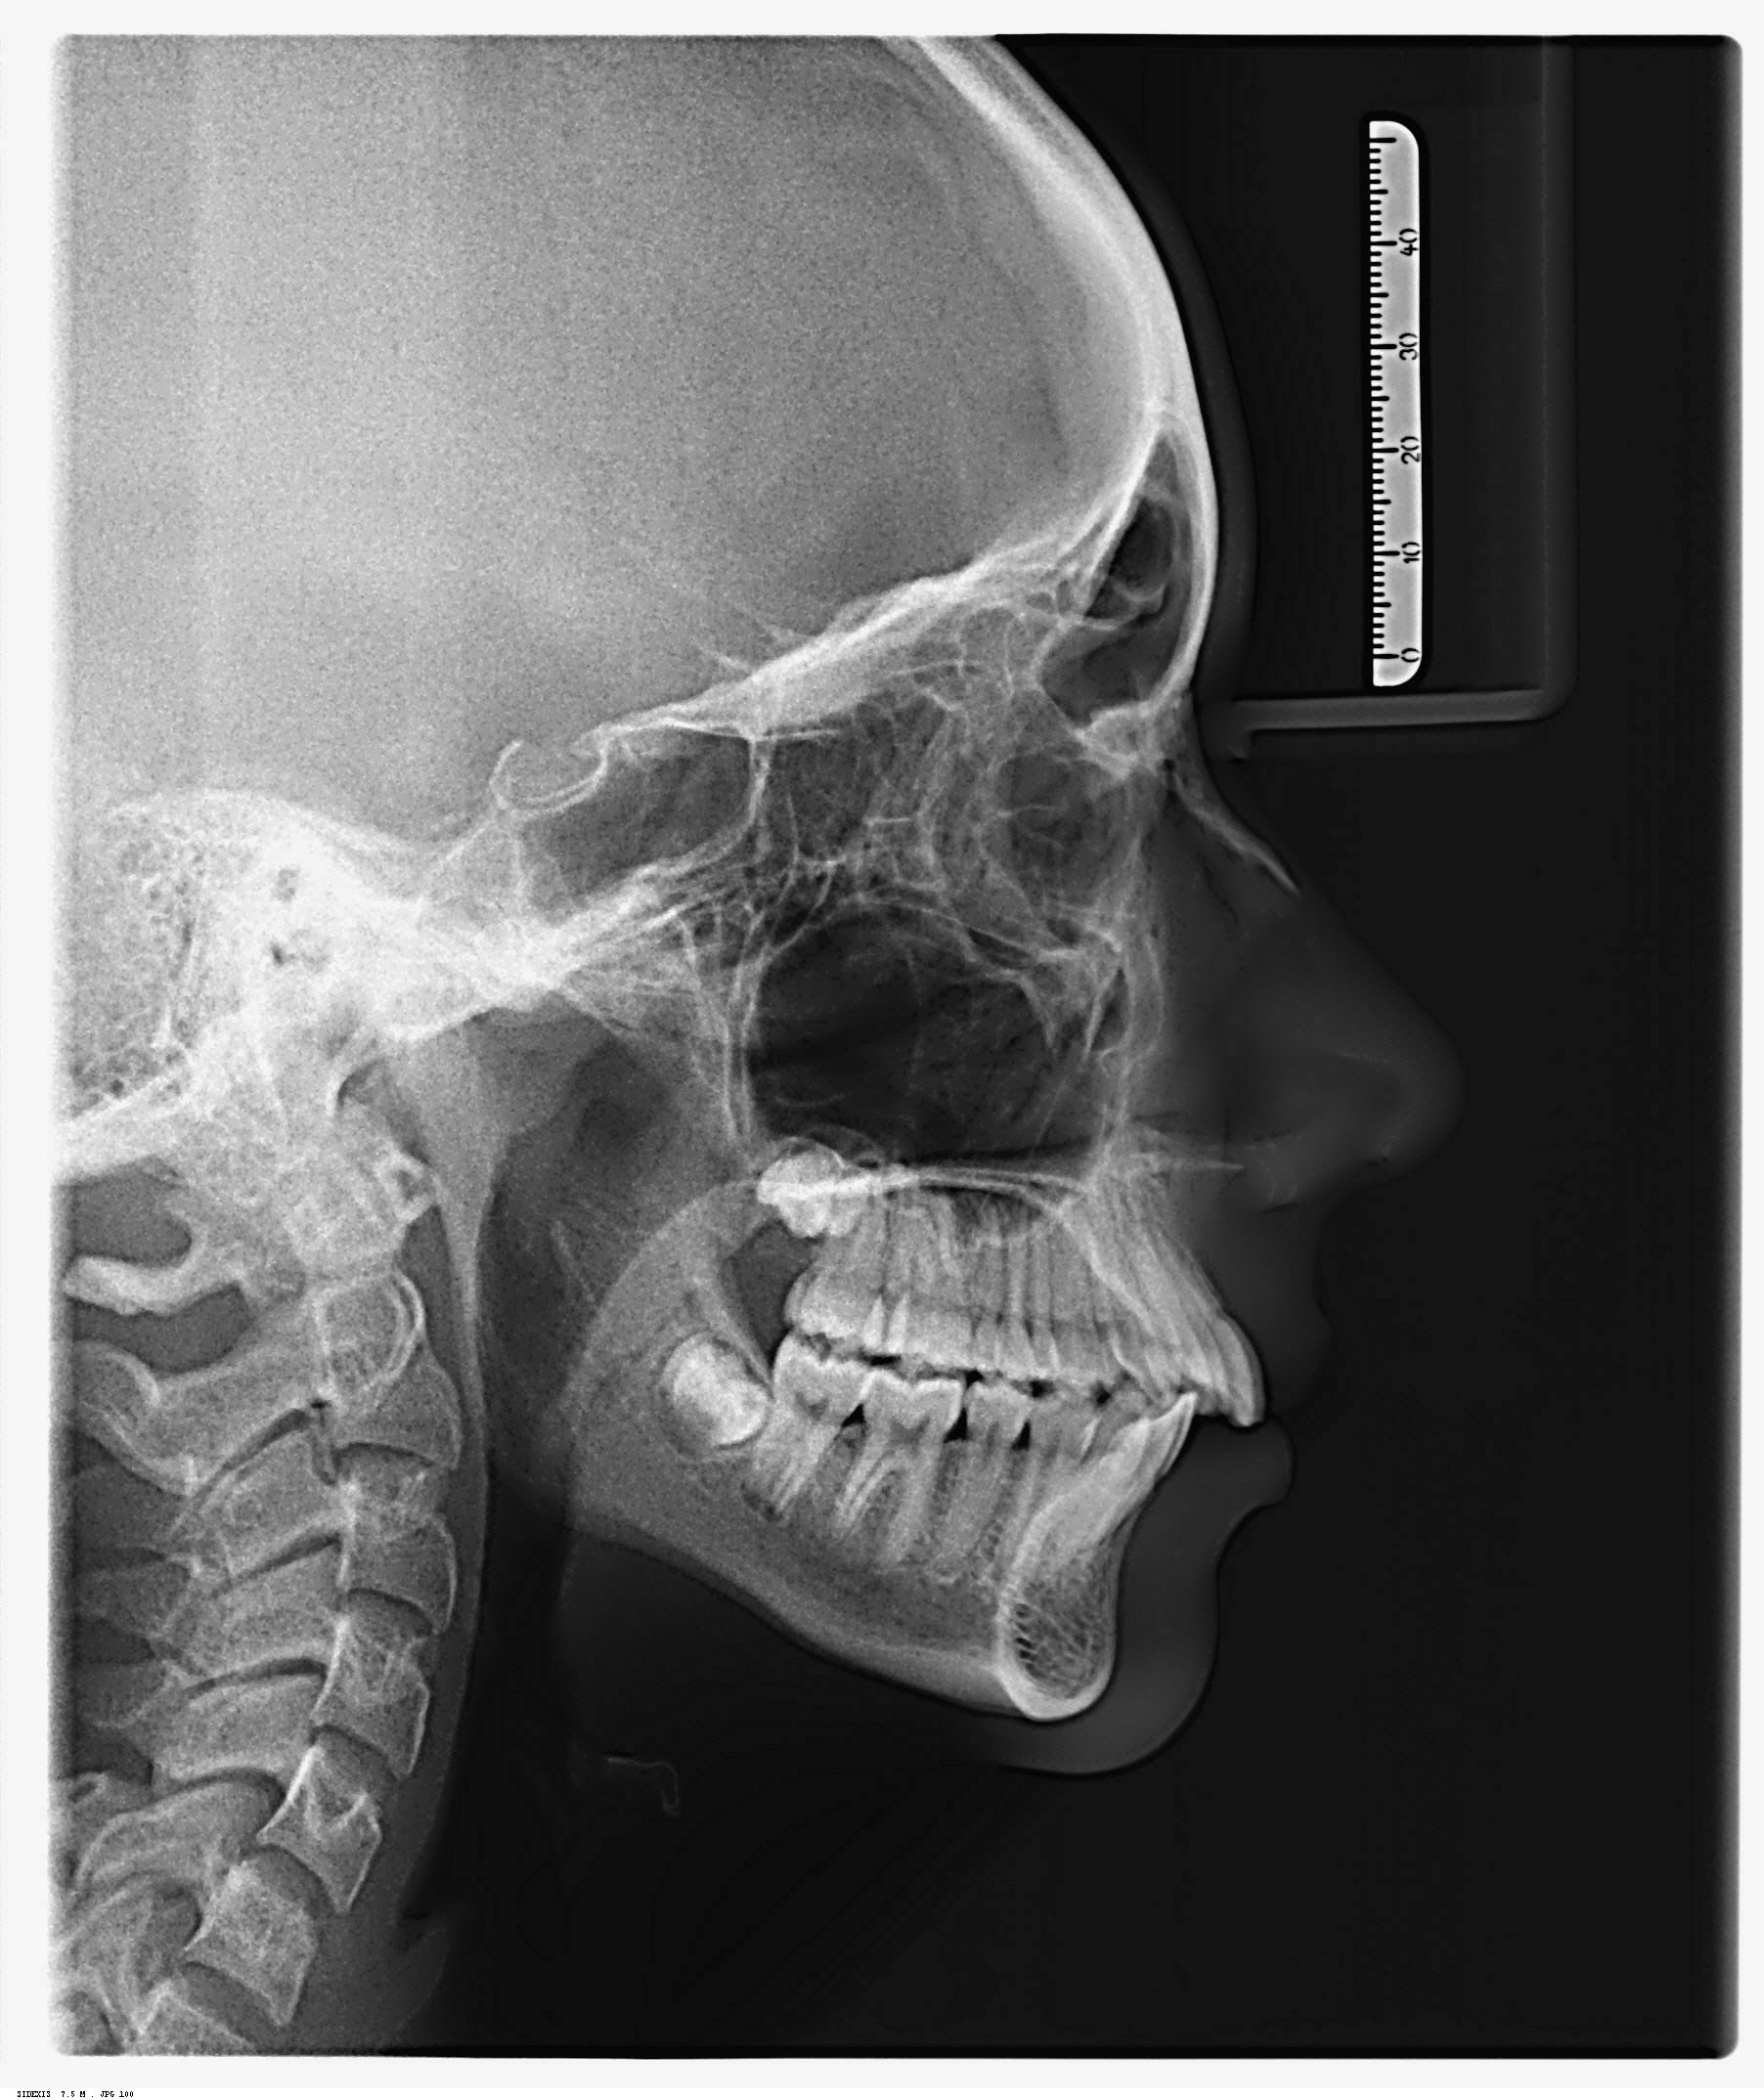

Telerradiografia